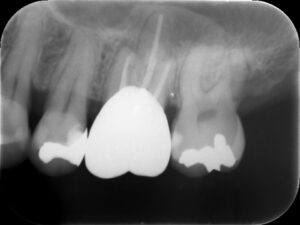

初診時レントゲン。他院にて根管治療を数か月行っているが痛みが続いていると訴えて来院。根管内には依然に詰めた薬がまだ残っているように見える。根尖部の骨破壊はほとんど認めない。